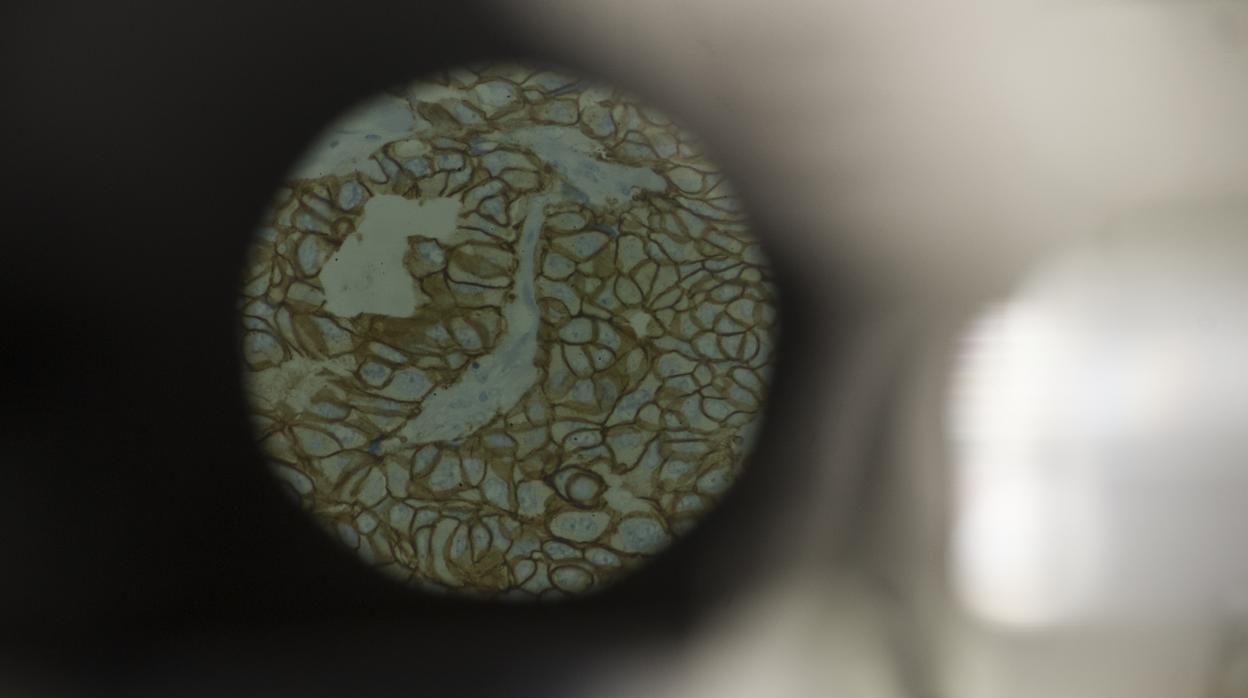

Vista a microscopio de una muestra de tumor de mama INÉS BAUCELLS